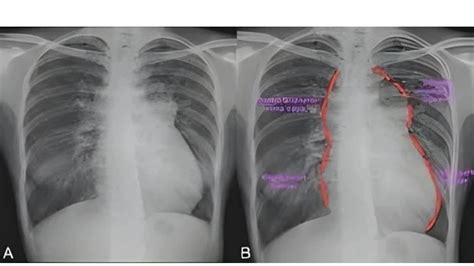

Total Anomalous Pulmonary Venous Return (TAPVR) overview

Pediatric Cardiology : Total Anomalous Pulmonary Venous Connection ...